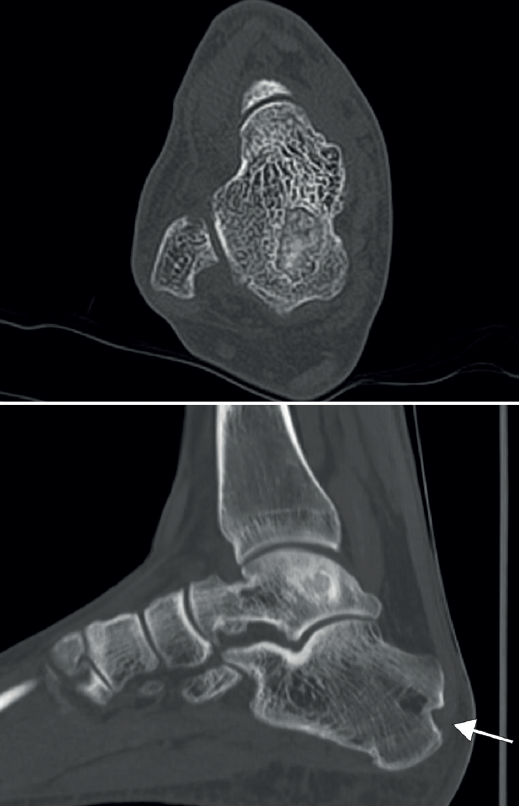

Se presenta el caso de un varón de 33 años con clínica de dolor y limitación funcional en el tobillo derecho de 3 años de evolución. Los estudios por imagen mostraron una lesión de tipo quístico de 2 × 1 ×2,3 cm (diámetros anteroposterior, transversal y craneocaudal), de márgenes geográficos, en el cuerpo del astrágalo, con extensiones filiformes a la articulación tibioastragalina, a nivel de la cúpula medial, que fue orientado en las pruebas radiográficas iniciales como un posible ganglión intraóseo (Figura 1).

Se amplió el estudio con imágenes de la tomografía axial computarizada (TAC) que mostraron su extensión subcondral (Figura 3).